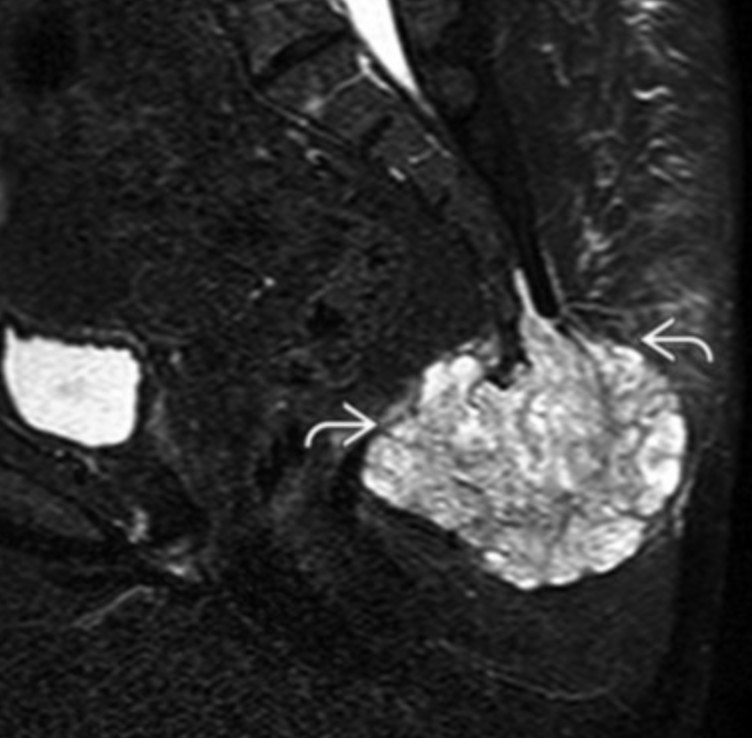

Synovial Sarcoma

• Misnomer as does not actually arise from synovium or in the joint but typically adjacent to joint

• Strong predilection for the extremities

• Relatively young 15-40 yo

• Slow growing and does not have to be painful

• Calcifications about 1/3 of the time

• Not required but commonly located next to a neurovascular bundle (popliteal space, anterior shoulder for example)

• Triple sign

• 3 different densities

• Looks like teratoma in the soft tissue, sometimes, other times just looks like a fucked up mass

• Split fat sign

• Very thin line of fat along periphery of mass, very subtle

• Heterogenous on MR with internal necrosis